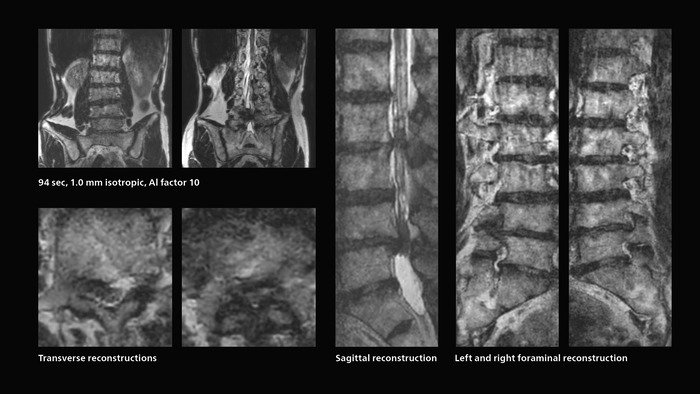

Faster lumbar spine exams are beneficial for patients with pain

Many patients who must undergo a lumbar spine examination suffer from back pain. For these patients it is difficult to maintain the imaging position long enough to successfully complete the examination. “In such cases, using SmartSpeed allows us to perform volume imaging, so that we acquire only one high resolution 3D sequence in a short time and then reconstruct the other orientations from that,” Dr. Katahira says. “This is highly advantageous because the patient needs only endure a short exam time, whereas before it was necessary to acquire a larger number of sequences in total. We have seen that the shorter time has allowed us to scan patients who previously could not finish the exam. This is a great advantage.”

Fast lumbar spine imaging for successful exam of patient in pain

A patient arrived saying that undergoing MRI was not possible because of severe back pain and leg pain, was imaged with SmartSpeed in only 94 seconds. The scan was diagnostic and afterwards the patient confirmed that it only took a little while. Performed on Elition X.

The hospital’s fast lumbar spine ExamCard includes T2W SpineVIEW, 1:40 min, 1.0 mm isotropic, acceleration factor 12.